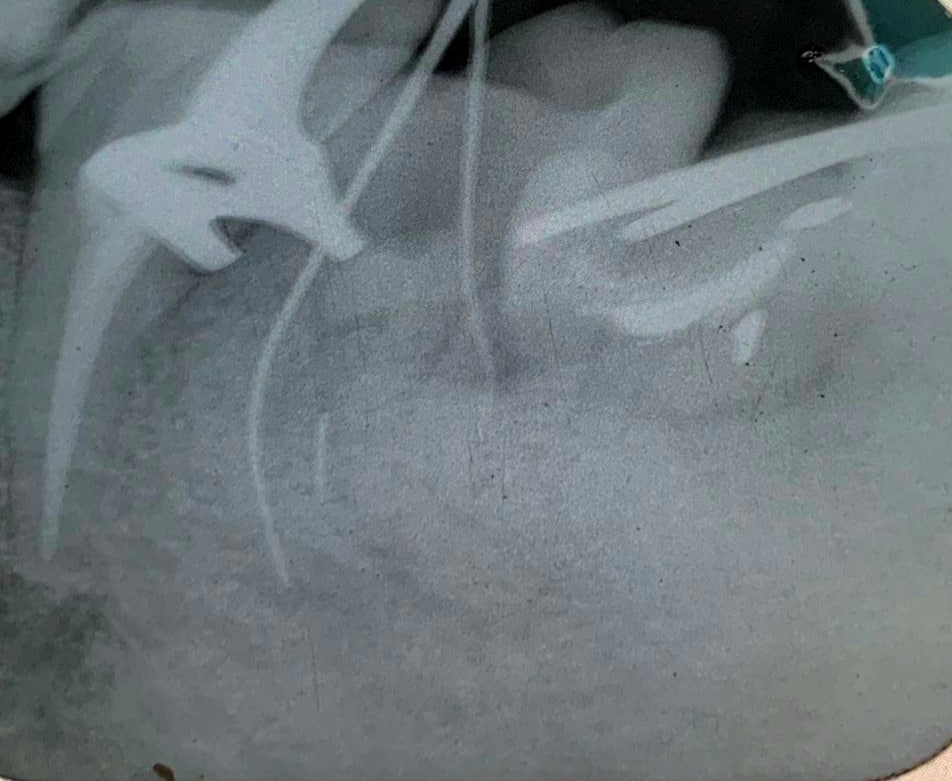

Patient came to our hospital with pulpotec restoration on lower 6 and the tooth shows alot of signs and symptoms & peri apical pathosis related to mesial and distal roots , by radiographic and clinical examination it revealed that :

1-broken file found in mesiobuccal root

2-ledge in mesiolingual root

3- calcification and ledge in distobuccal root

-Bybassing MB broken file then overcoming calcification of DB and two ledges in DB&ML canals &finally obturating 4 canals successfully by using gutta percha and bioceramic sealer

Broken file bypass in MB canal

Ledge in ML, Ledge and calcificaton in DB.

ML ledge bypass

DB ledge bypass ,calcification mangement , master cone

Obturation with single cone and bioceramic sealer